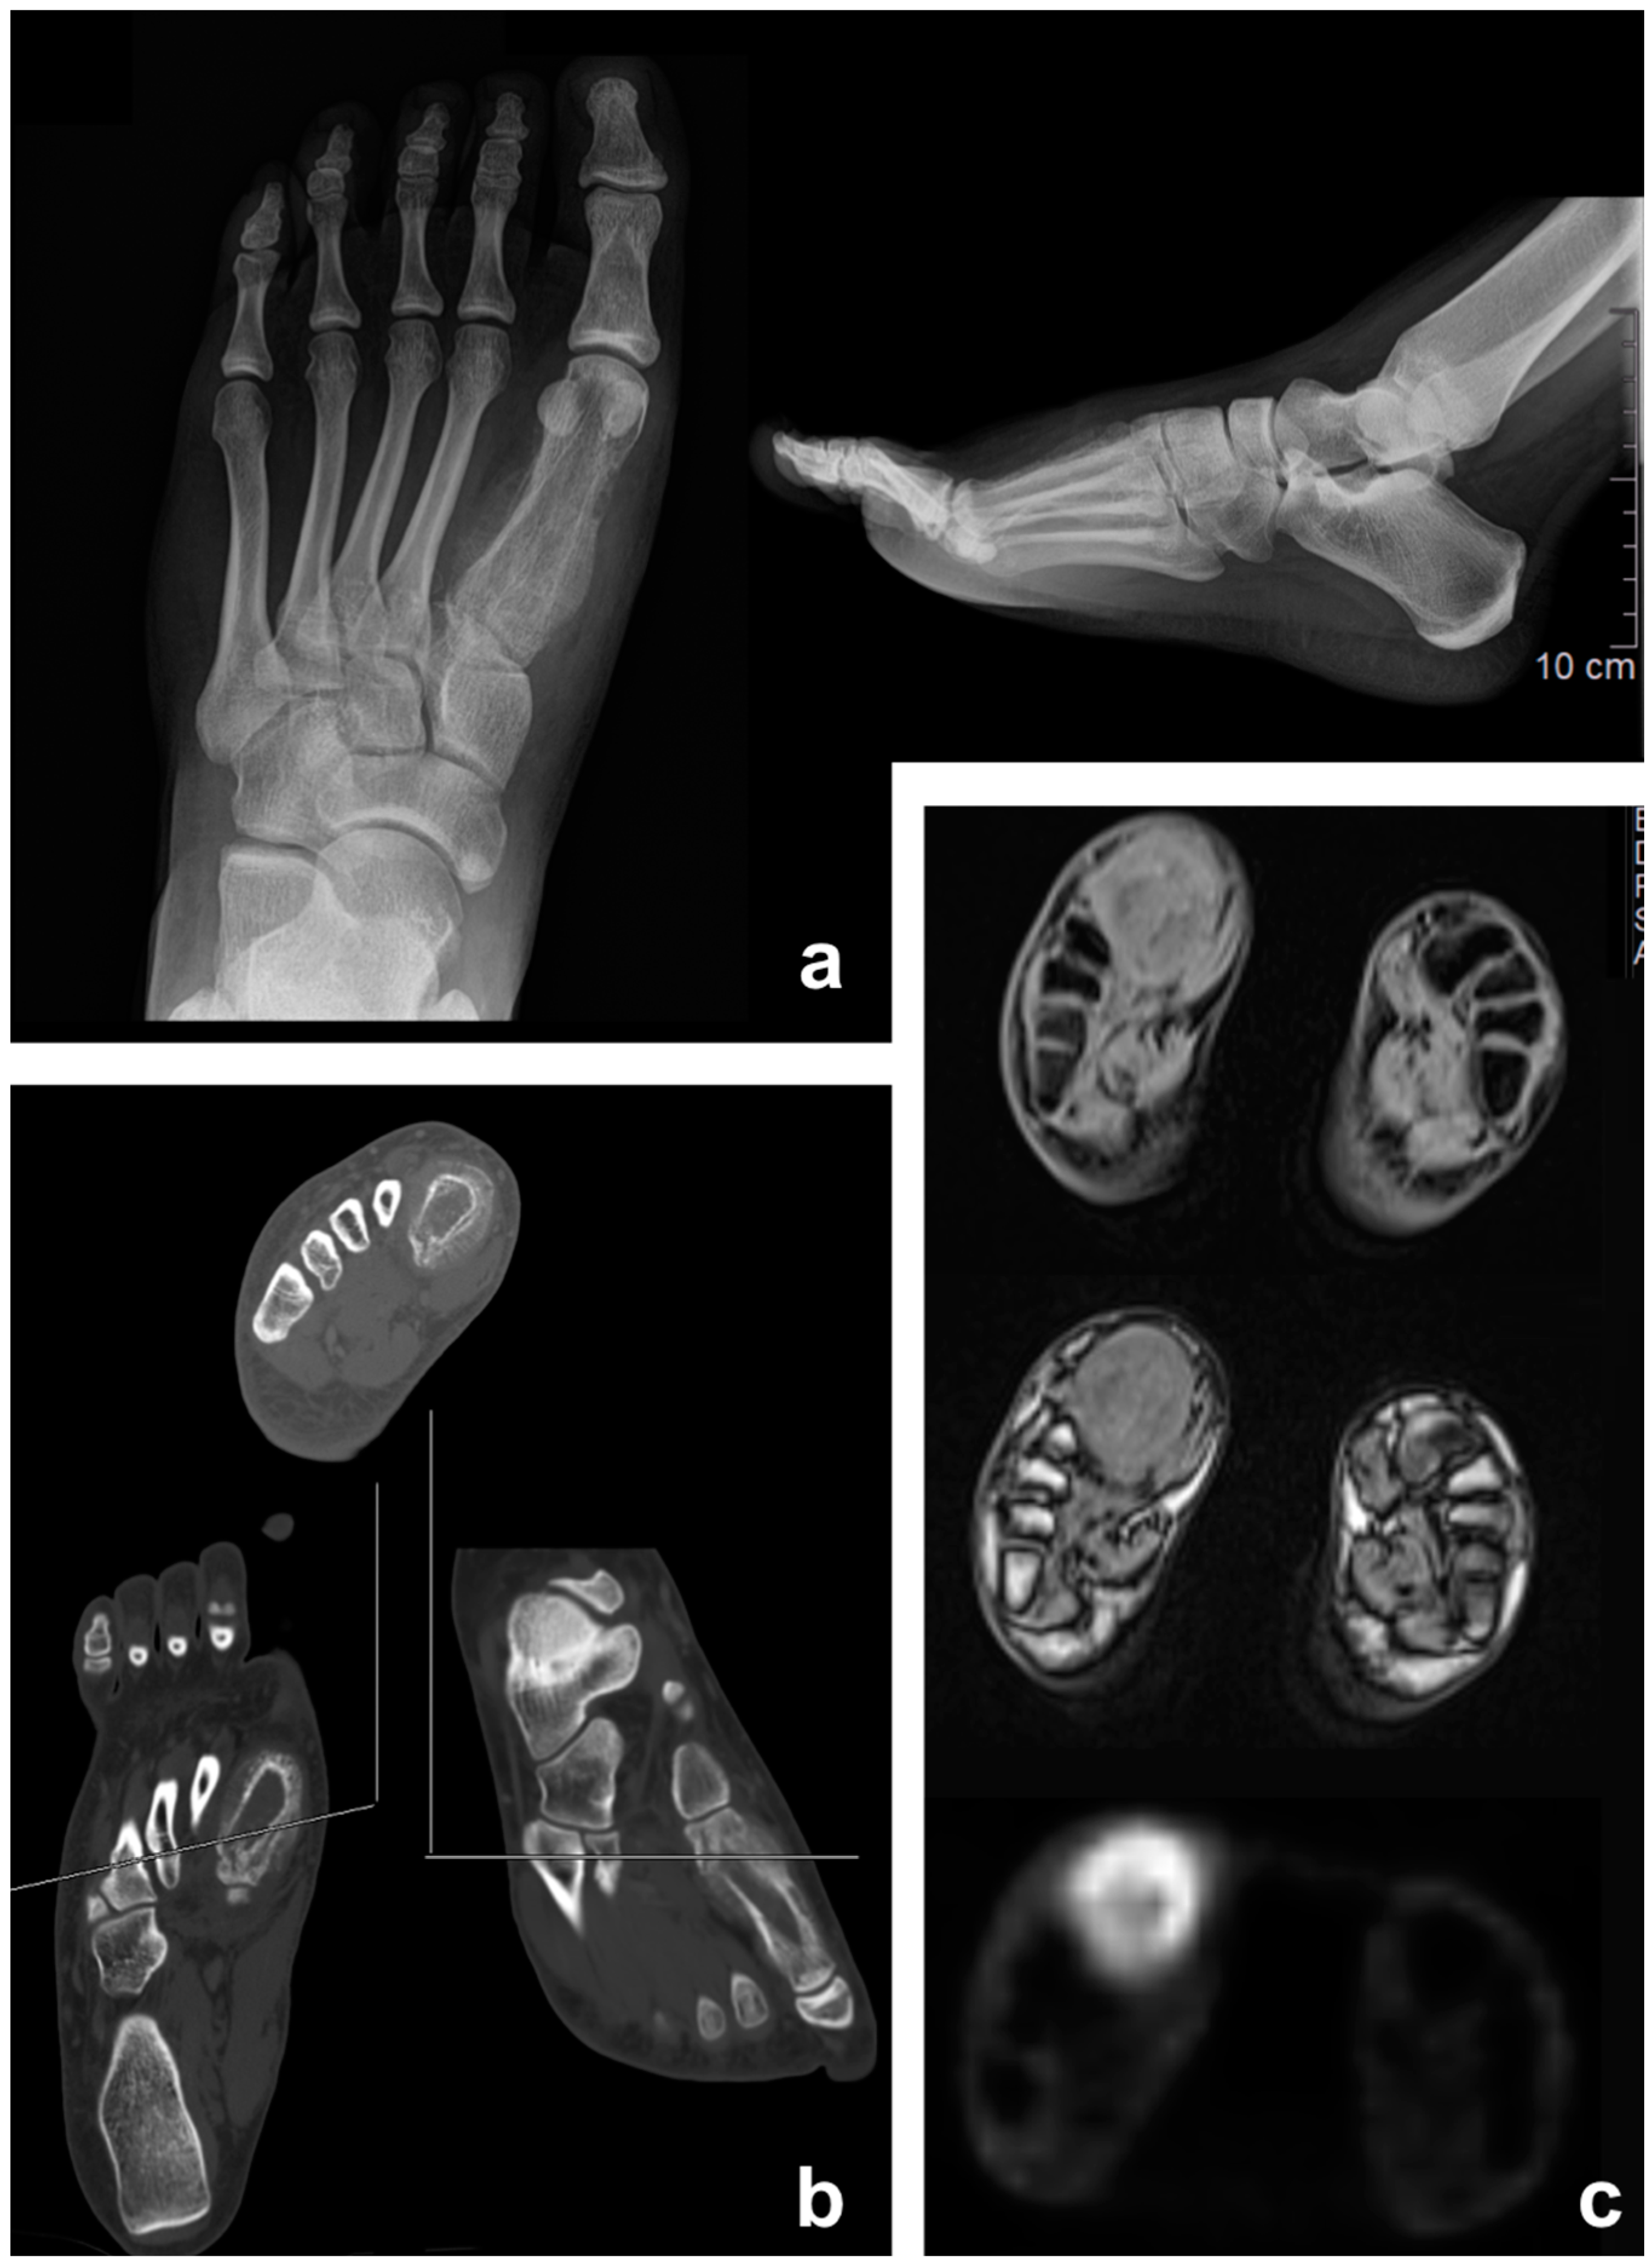

3.2. Chondrosarcoma